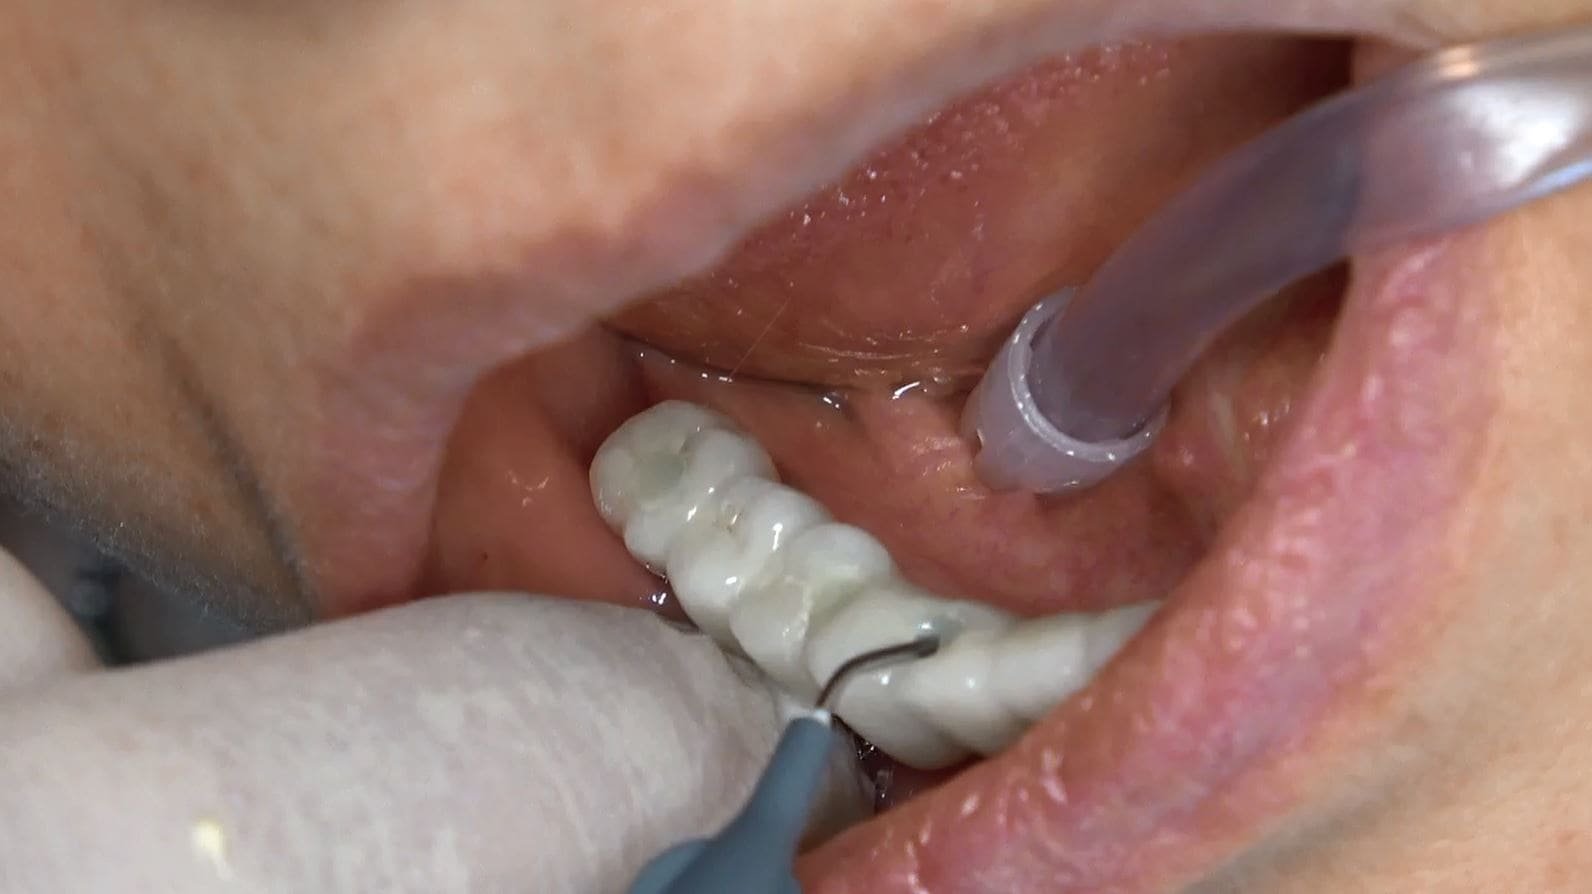

• Una delle caratteristiche distintive di questa tecnica è il carico immediato. Subito dopo l’inserimento della griglia e degli impianti, viene applicata una protesi dentale fissa provvisoria, consentendoti di avere denti fissi fin dalla stessa giornata dell’intervento.

• Dopo un periodo di circa 6 mesi, quando l’integrazione degli impianti è completa, la protesi provvisoria può essere sostituita con una protesi dentale fissa definitiva in ceramica, composta da 14 denti.

Passati 6 mesi di osteointegrazione si sostituisce protesi fisse provvisorie con protesi fisse in ceramica definitiva 14 denti